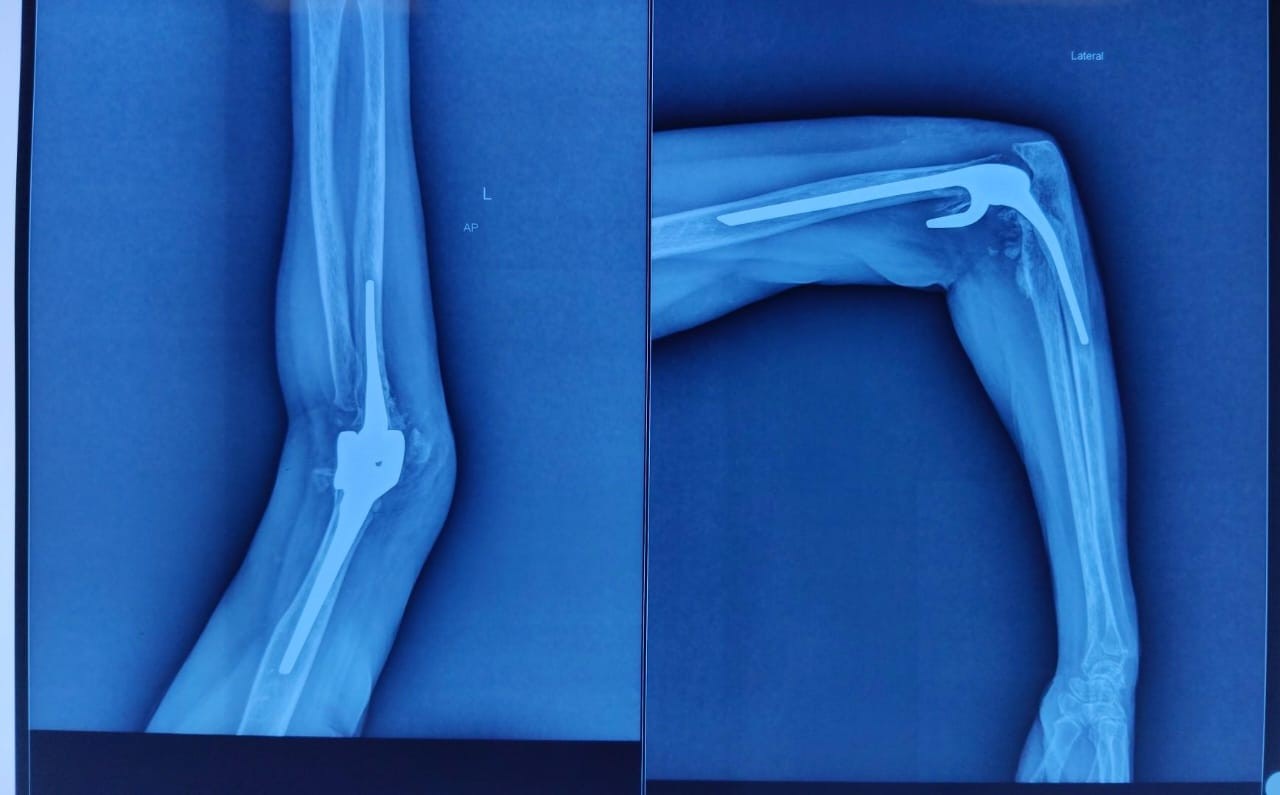

Figure 3: Reconstruction and anatomical replication.

Pain-free with complete resolution of paraesthesia with DASH score, which improved from 65 (pre-operative) to 15.3 (at the end of 1 year). Radiographs at 6 weeks, 6 months, and 1 year revealed no aseptic loosening of the elbow prosthesis along with non-displacement of both the condyles. (Figure 6,7,8)

Figure 6: Post-operative radiograph.

Figure 7: Post-operative radiograph.

Figure 8: Follow-up radiograph.